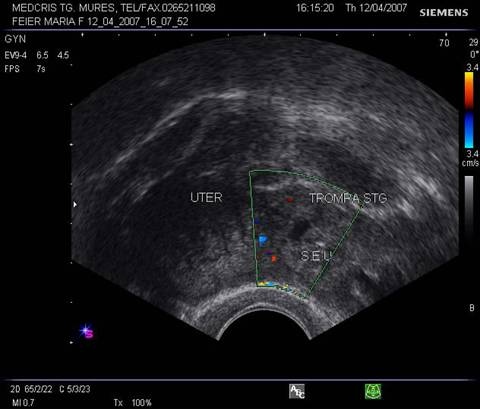

Fig nr 62 Sectiune transversala la nivel corpului uterin , la ecografia transvaginala. Parauterin, in trompa stg., se evidentiaza o formatiune inomogena cu ecou hipoecogen relativ central

![]()